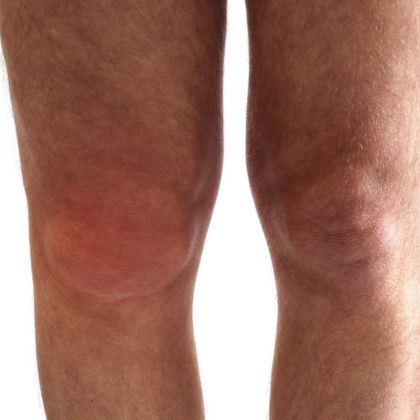

Wczesne objawy nowotworów kości mogą być łatwo przeoczone lub zinterpretowane jako zwykłe dolegliwości. Na co zwrócić uwagę:

- Obrzęk w okolicach stawów lub kości.

W zaawansowanym stadium nowotworu kości objawy mogą być bardziej nasilone i obejmować:

- Nasilający się ból, który może być obecny zarówno w spoczynku, jak i podczas ruchu.

- Zmiany skórne nad obszarem dotkniętym nowotworem kości.